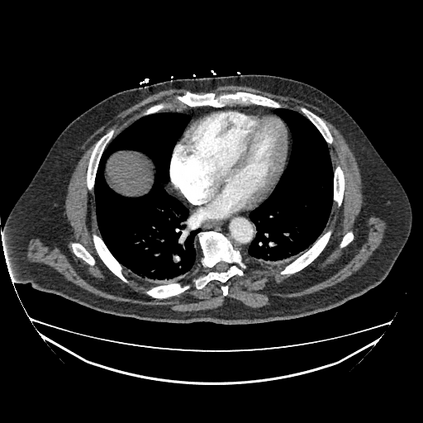

In this study, we aim to initiate the development of Radiology Foundation Model, termed as RadFM.We consider the construction of foundational models from the perspectives of data, model design, and evaluation thoroughly. Our contribution can be concluded as follows: (i), we construct a large-scale Medical Multi-modal Dataset, MedMD, consisting of 16M 2D and 3D medical scans. To the best of our knowledge, this is the first multi-modal dataset containing 3D medical scans. (ii), We propose an architecture that enables visually conditioned generative pre-training, allowing for the integration of text input interleaved with 2D or 3D medical scans to generate response for diverse radiologic tasks. The model was initially pre-trained on MedMD and subsequently domain-specific fine-tuned on RadMD, a radiologic cleaned version of MedMD, containing 3M radiologic visual-language pairs. (iii), we propose a new evaluation benchmark that comprises five tasks, aiming to comprehensively assess the capability of foundation models in handling practical clinical problems. Our experimental results confirm that RadFM significantly outperforms existing multi-modal foundation models. The codes, data, and model checkpoint will all be made publicly available to promote further research and development in the field.